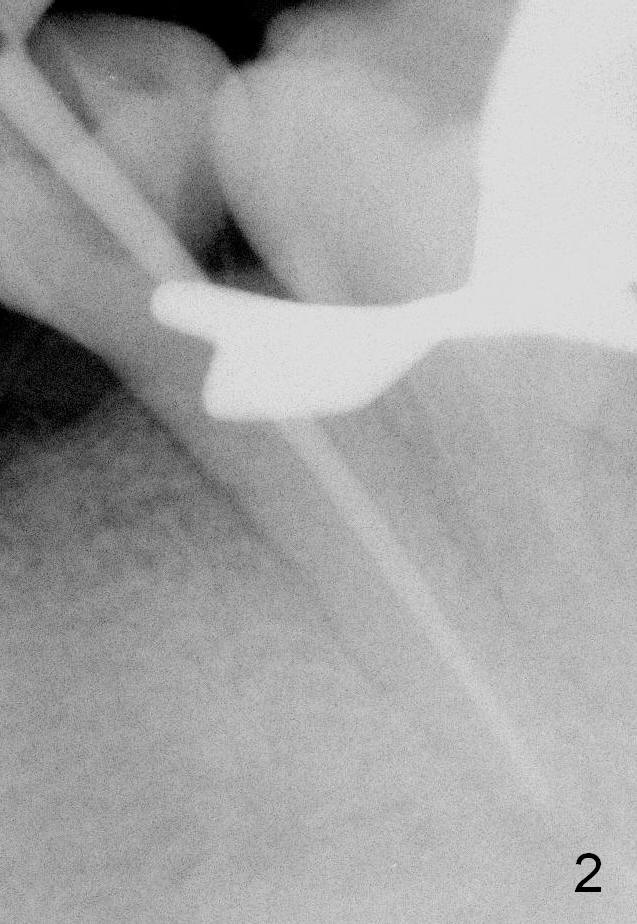

A 56-year-old man has poor dentition (Fig.1). The tooth #20 fractures (not shown) after root canal therapy (Fig.2). A 4.5x14 mm bone-level implant is planned (Fig.3).

CT sagittal section of a similar case shows that the root is also long, but curved (Fig.4). A 4.5x14 mm implant is slightly longer than the root. The apex of the implant has distance to the underlying nerve (N). The coronal section shows that the implant should be placed lingually (Fig.5 L), since the buccal (B) plate is thin (Fig.6 between arrowheads). The first drill (2 mm) is to be placed lingually (Fig.7 red arrow). When the implant is placed, there should be a buccal gap, to be filled with bone graft (Fig.5 red circles).

The 2nd drill will be 2.5 mm reamer (17 mm from the gingival margin). To placed the implant, use a latch driver, followed by latch adapt and torque wrench. If insertion torque is high (>45 Ncm), place cemented abutment (probably 5824 (Fig.3 green line (5.44 mm)) and fabricate an immediate provisional.